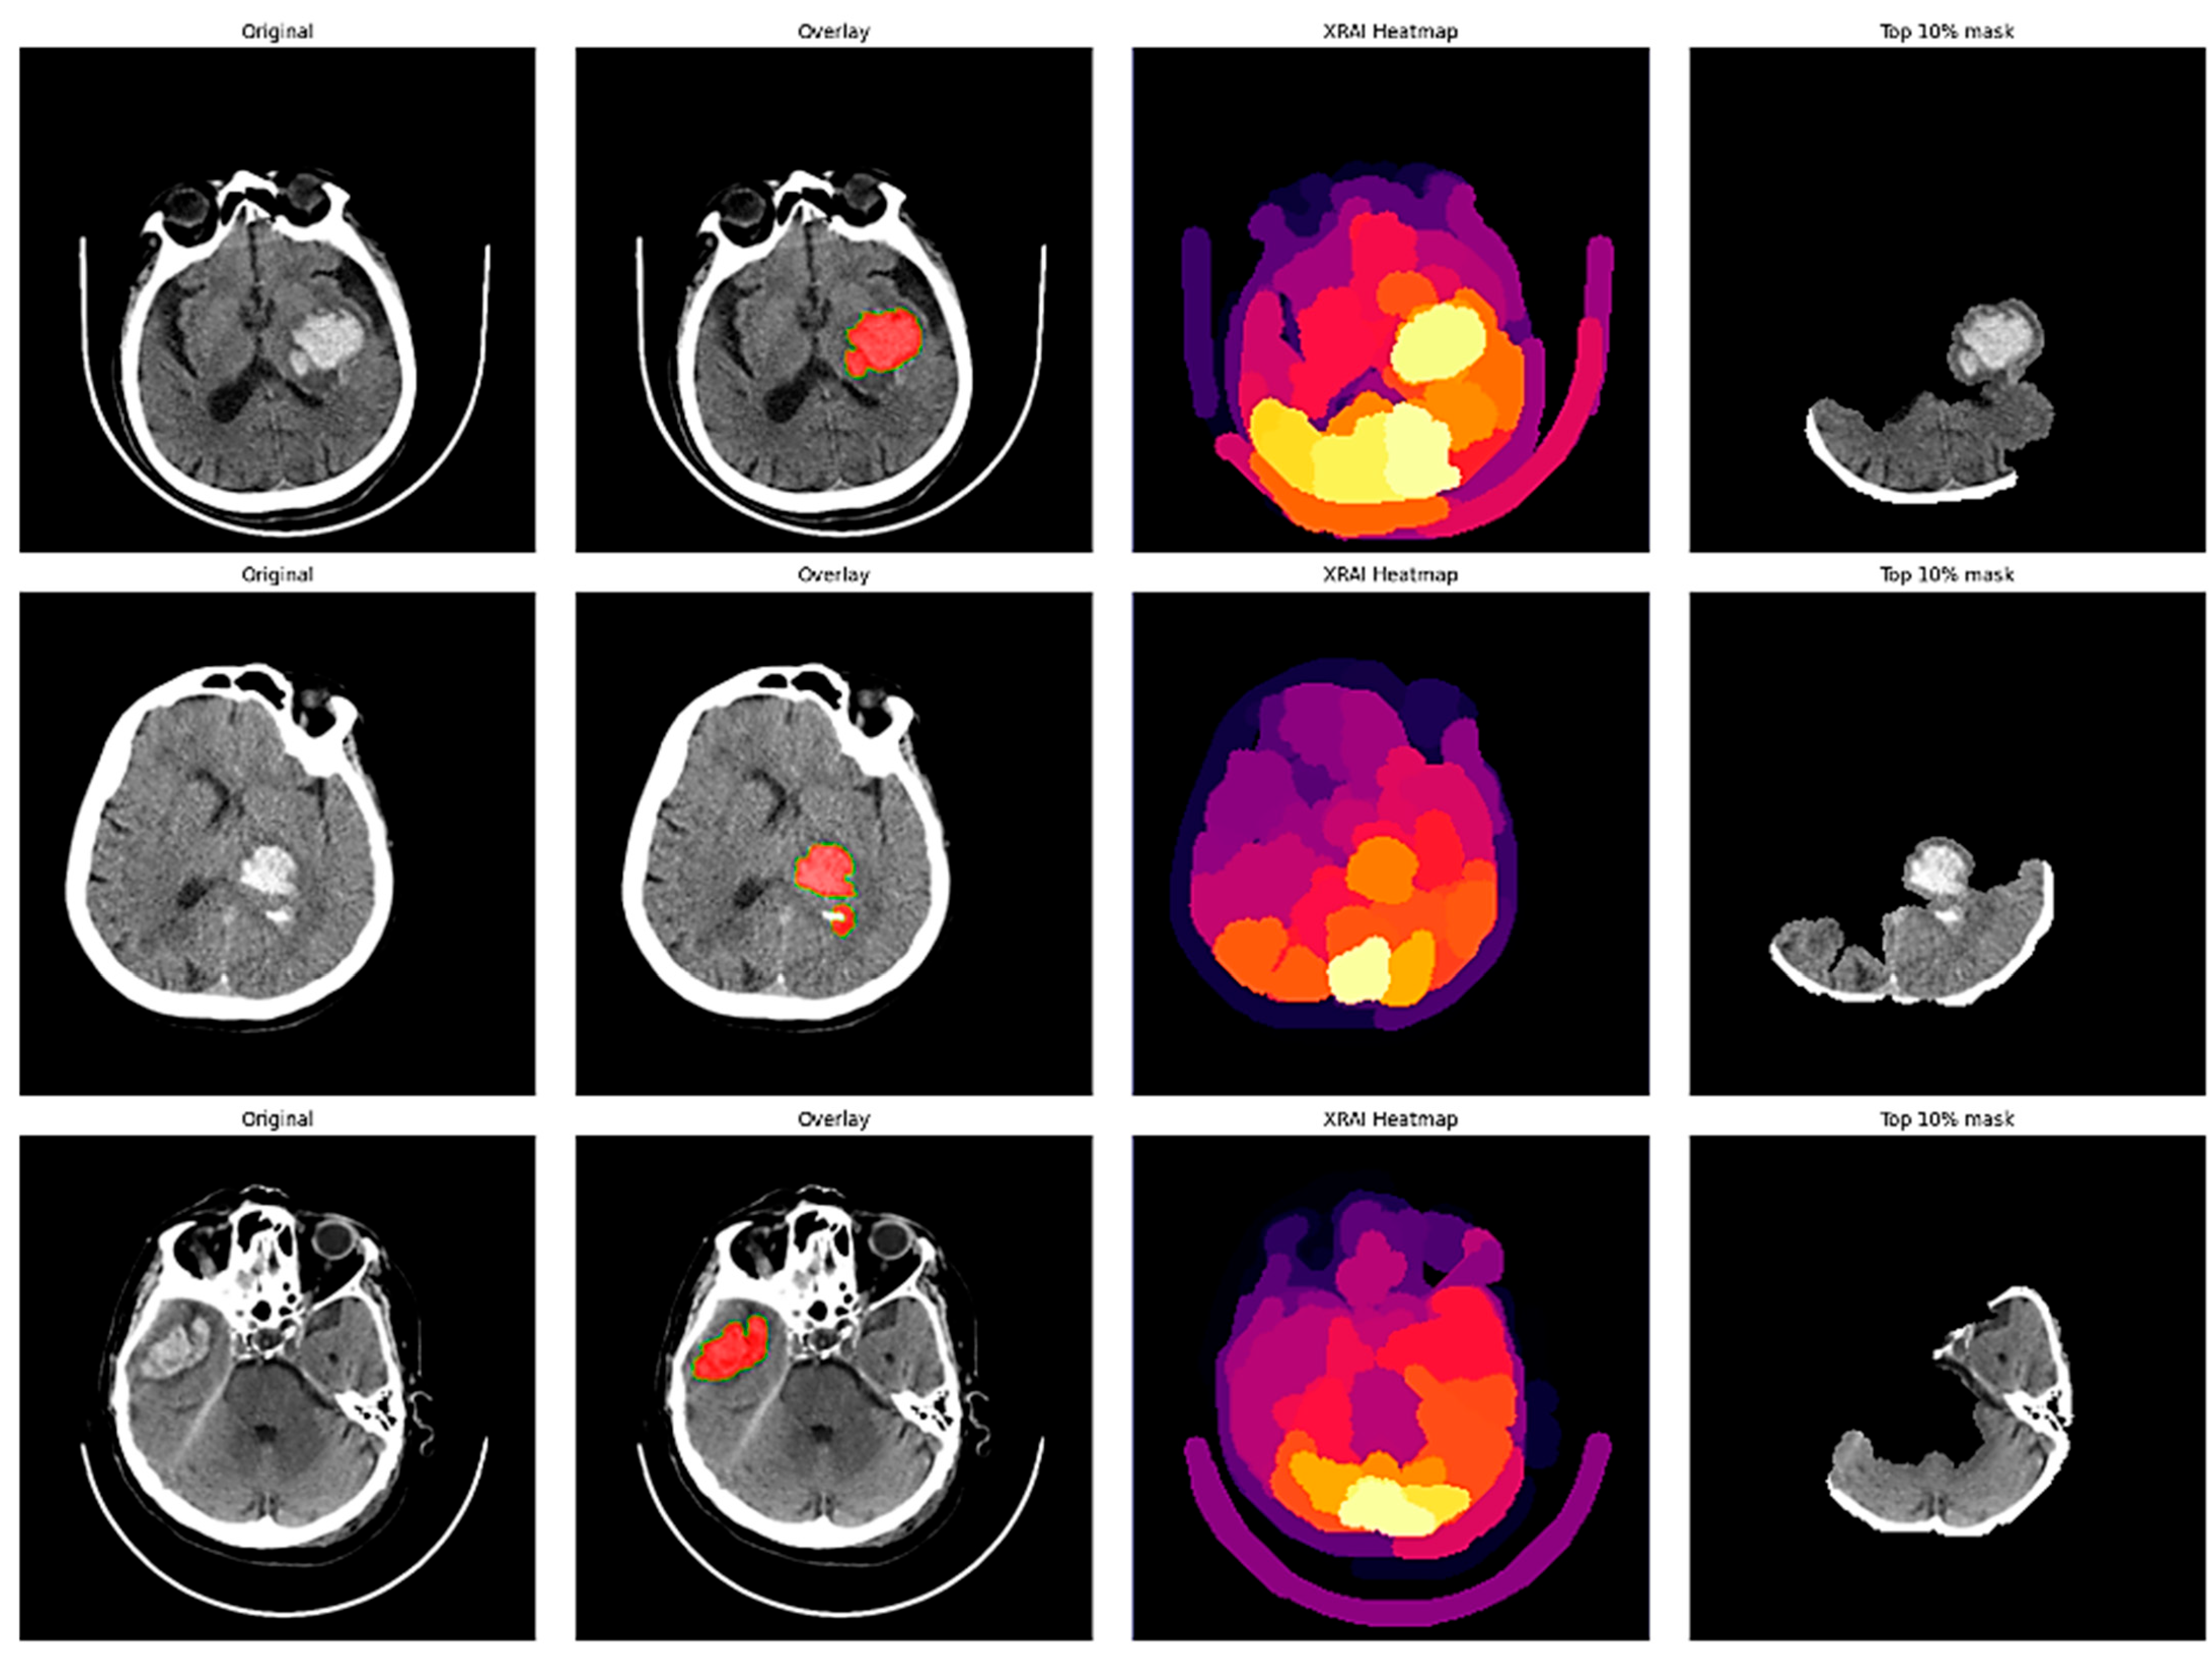

XRAI analysis of hemorrhagic stroke cases performed variably in lesion localization, with correct attribution in some cases and drastic disagreements with radiologist annotations in others (Figure 6).

In Figure 6, Case 1 shows an extensive left hemisphere hemorrhage, where the radiologist’s overlay cleanly delineates a large bleed in the left cerebral hemisphere, evident on the right side of the axial image. The XRAI heatmap delineates its strongest attributes, evidenced by highly saturated yellow areas, tightly grouped around the hemorrhagic region. The top 10% mask firmly demarcates the hemorrhagic center, showing the model appropriately draws attention to the primary site of bleeding for this clearly large hemorrhage.

Case 2 illustrates a smaller hemorrhage in the left hemisphere, which is again represented in the left hemisphere but on the right side of the image. The XRAI heatmap generally attributes this exact region while also implying weaker activation of the surrounding tissue. The top 10% mask neatly delineates the hemorrhagic core, thereby illustrating consistent localization capacity even for smaller bleeding events. This case indicates the model possesses the capability to efficiently detect compact hemorrhagic lesions.

However, Case 3 reveals a significant weakness in XRAI interpretation. The radiologist overlay unmistakably delineates a bleed in the right temporal lobe, which is on the image-left, but XRAI’s heatmap places its highest activations more dispersed around in the skull-base/cerebellar region than on true hemorrhage. Consequently, the top 10% mask delineates out that ventral area instead of the true location of bleeding. This discrepancy demonstrates that in this slice, the model is disproportionately attending to features like bone or artifact patterns at the base of the skull instead of hemorrhagic lesion detection.

5.1.2. Ischemic Stroke Cases Analysis

The XRAI analysis of the ischemic stroke cases illustrated ongoing challenge with the accurate detection of hypodense lesions, wherein the model invariably favored salient anatomical asymmetries over subtle tissue composition changes. In Figure 7, Case 1 is a small cortical infarct in the right hemisphere, wherein the radiologist overlay delineates a subtle hypodense lesion in the right frontal cortex, apparent on the left side of the axial image. However, the XRAI heatmap reveals its greatest activations along the superior calvarial margin rather than over the lesion itself. Moreover, the top 10% mask only emphasizes that skull-margin region. This pattern of observation indicates that XRAI has trouble with low-contrast ischemic tissue and instead emphasizes the sharply defined interfaces between brain and bone.

Case 2 has a large left-hemisphere infarct with clearly demarcated borders extending across the left cerebral hemisphere, readily apparent on the image-right radiologist overlay. The XRAI heatmap does show increased overall activation on the brain side ipsilateral to the stroke, showing some sensitivity to the infarcted region. The peak points remain, however, at the ventral skull base and cortex borders and not in the hypodense parenchyma. Again, then, the top 10% mask shows high-contrast bone-air interfaces and not parenchymal hypodensity. Although XRAI in this case does have a bias toward the correct hemisphere, it essentially mislocalizes the central lesion.

Case 3 continues the trend with a moderate-severity right-hemisphere insular infarct. The overlay marks a hypodense area in the right temporal lobe image-left, but the XRAI heatmap spreads its highest activations across the posterior fossa and the edges of the calvarium. The top 10% mask again selects bone edges rather than the infarct itself. This identical trend with the ischemic cases indicates that for more subtle or tissue-deep lesions, XRAI also prefers high-contrast anatomical landmarks.

This tendency to emphasize skull-base or calvarial regions rather than lesions likely arises from two factors: (1) the sharp bone–air interfaces and dense cortical bone margins create strong pixel intensity gradients that saliency methods such as XRAI may interpret as predictive, especially when lesion contrast is low, and (2) potential dataset-driven correlations between certain anatomical boundaries and pathology labels that may have led the model to occasionally associate these regions with diagnostic classes. These effects are more pronounced in ischemic cases where hypodense lesions have inherently lower signal-to-noise ratios compared to hemorrhages. While this does not necessarily indicate a misclassification, it reflects a limitation of current attribution techniques, which may not always align perfectly with the underlying pathology. Future work will explore attribution refinement strategies such as lesion-masked saliency computation or gradient regularization to improve localization fidelity.

Figure 6. XRAI Analysis of Hemorrhagic Stroke.

Figure 7. XRAI Analysis of Ischemic Stroke.